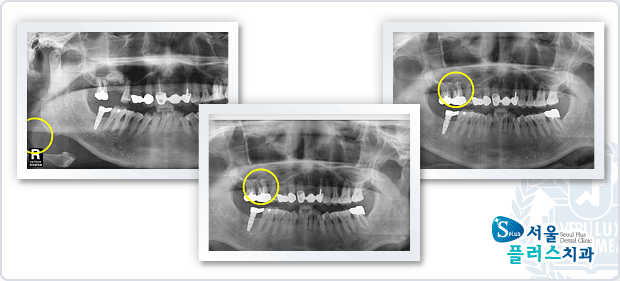

[임플란트] 임플란트 - 염증이 심한 치아 발치 후 뼈 이식후 3개월 기다렸다 임플란트 식립